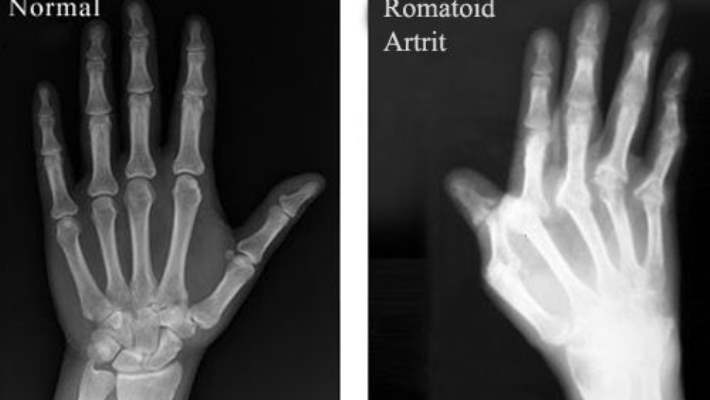

Eklem İltihabı ve Tetik Parmak Hastalığı